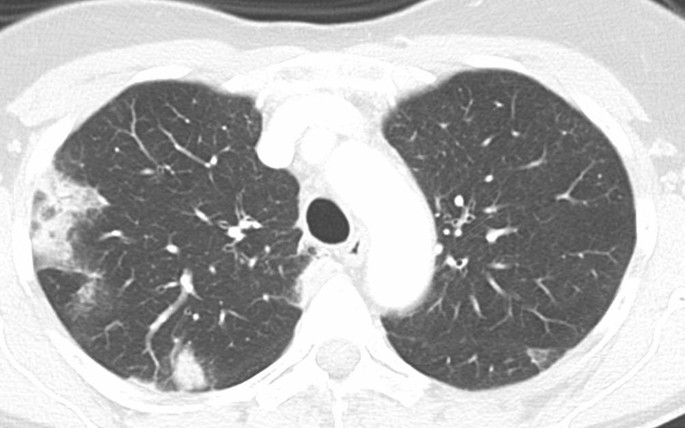

In der Thorax-CT zeigen sich initial am häufigsten Milchglasverdichtungen mit oder ohne Konsolidierungsareale (Abb. 23 und 4; [20, 21]). Konsolidierungsareale können auch ohne Milchglasverdichtungen vorkommen oder ein zentrales Milchglasareal im Sinne eines „umgekehrtes Halo-Zeichen“ umgeben [20, 21]. Gelegentlich zeigen sich verdickte Interlobärsepten, teilweise gemeinsam mit Milchglas („crazy paving“; [20]). Die Lungenparenchymveränderungen treten typischerweise bilateral, multifokal und in einer subpleuralen bzw. peripheren Verteilung auf, wobei oft eine (geringe) Prädominanz basaler und dorsaler Lungenabschnitte vorliegt [20, 21]. Die Veränderungen reichen von kleinen, rundlichen Arealen bis zu großflächigen Parenchymverdichtungen [20, 21]. Für COVID-19 nichttypische Manifestationen inkludieren Lymphadenopathie, Kavitationen oder noduläre Verteilungsmuster wie Tree-in-bud-Noduli [20, 21]. Pleuraergüsse sind selten [20, 21]. Letztere Veränderungen sind oft hinweisend auf das Vorliegen einer anderen Erkrankung oder einer Komplikation im Rahmen einer COVID-19-Pneumonie, wie z. B. eine kardiale Mitbeteiligung oder eine bakterielle Pneumonie.

Abb. 2

figure 2

Computertomogramm eines 34 Jahre alten Patienten mit Fieber und trockenem Husten. Peripher betonte Milchglasverdichtungen beidseits (rechts deutlich mehr als links) mit peripherer Betonung. Der Verdacht auf COVID-19 wurde durch eine PCR („polymerase chain reaction“) bestätigt